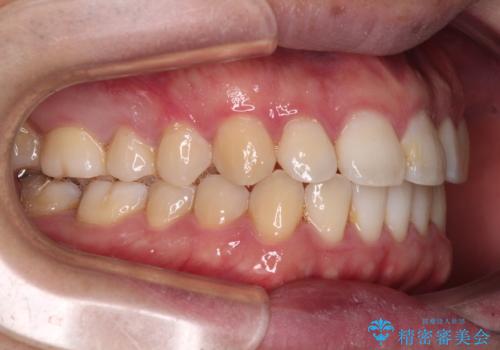

インビザラインで奥歯の咬み合わせと前歯のデコボコを改善

- 前歯のデコボコと奥歯の咬み合わせを気にして来院された患者様です。

前歯のデコボコはインビザラインで十分に対応可能と判断できましたが、咬合力が強いため、臼歯(特に右側)の交叉咬合はインビザライン単体では困難と思われました。

まずはインビザライン単体で矯正治療を開始し、交叉咬合が改善されない場合にはアンカースクリューなどの使用を検討することとしました。

インビザライン単体では右側の交叉咬合を解消することができなかったため、アンカースクリューを併用して咬合を改善させました。